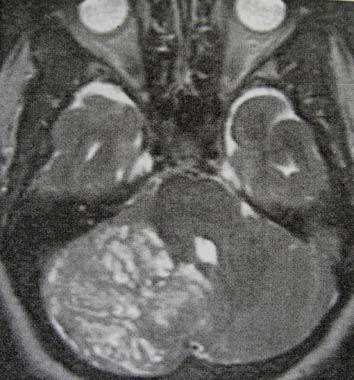

Petunjuk: Seorang laki-laki usia 16 tahun dengan hasil MRI sebagaimana ditunjukkan di bawah ini, dirujuk ke kantor anda. Hasil pemeriksaan laboratorium pasien mengungkapkan bahwa dia menderita hipotirodisme, kekurangan kortisol dan kadar prolaktin sebesar 69. Keluarganya mengatakan bahwa mereka mencatat adanya berbagai perubahan perilaku dan baru-baru ini mengalami kenaikan berat badan. Mata kirinya tidak bisa melihat dan lapang pandangan temporal mata kanannya terputus.

C. Kraniofaringioma

PERTANYAAN 44 - 45

Petunjuk: Seorang laki-laki usia 16 tahun dengan hasil MRI sebagaimana ditunjukkan di bawah ini, dirujuk ke kantor anda. Hasil pemeriksaan laboratorium pasien mengungkapkan bahwa dia menderita hipotirodisme, kekurangan kortisol dan kadar prolaktin sebesar 69. Keluarganya mengatakan bahwa mereka mencatat

adanya berbagai perubahan perilaku dan baru-baru ini mengalami kenaikan berat badan. Mata kirinya tidak bisa melihat dan lapang pandangan temporal mata kanannya terputus.

B. Efek Stalk